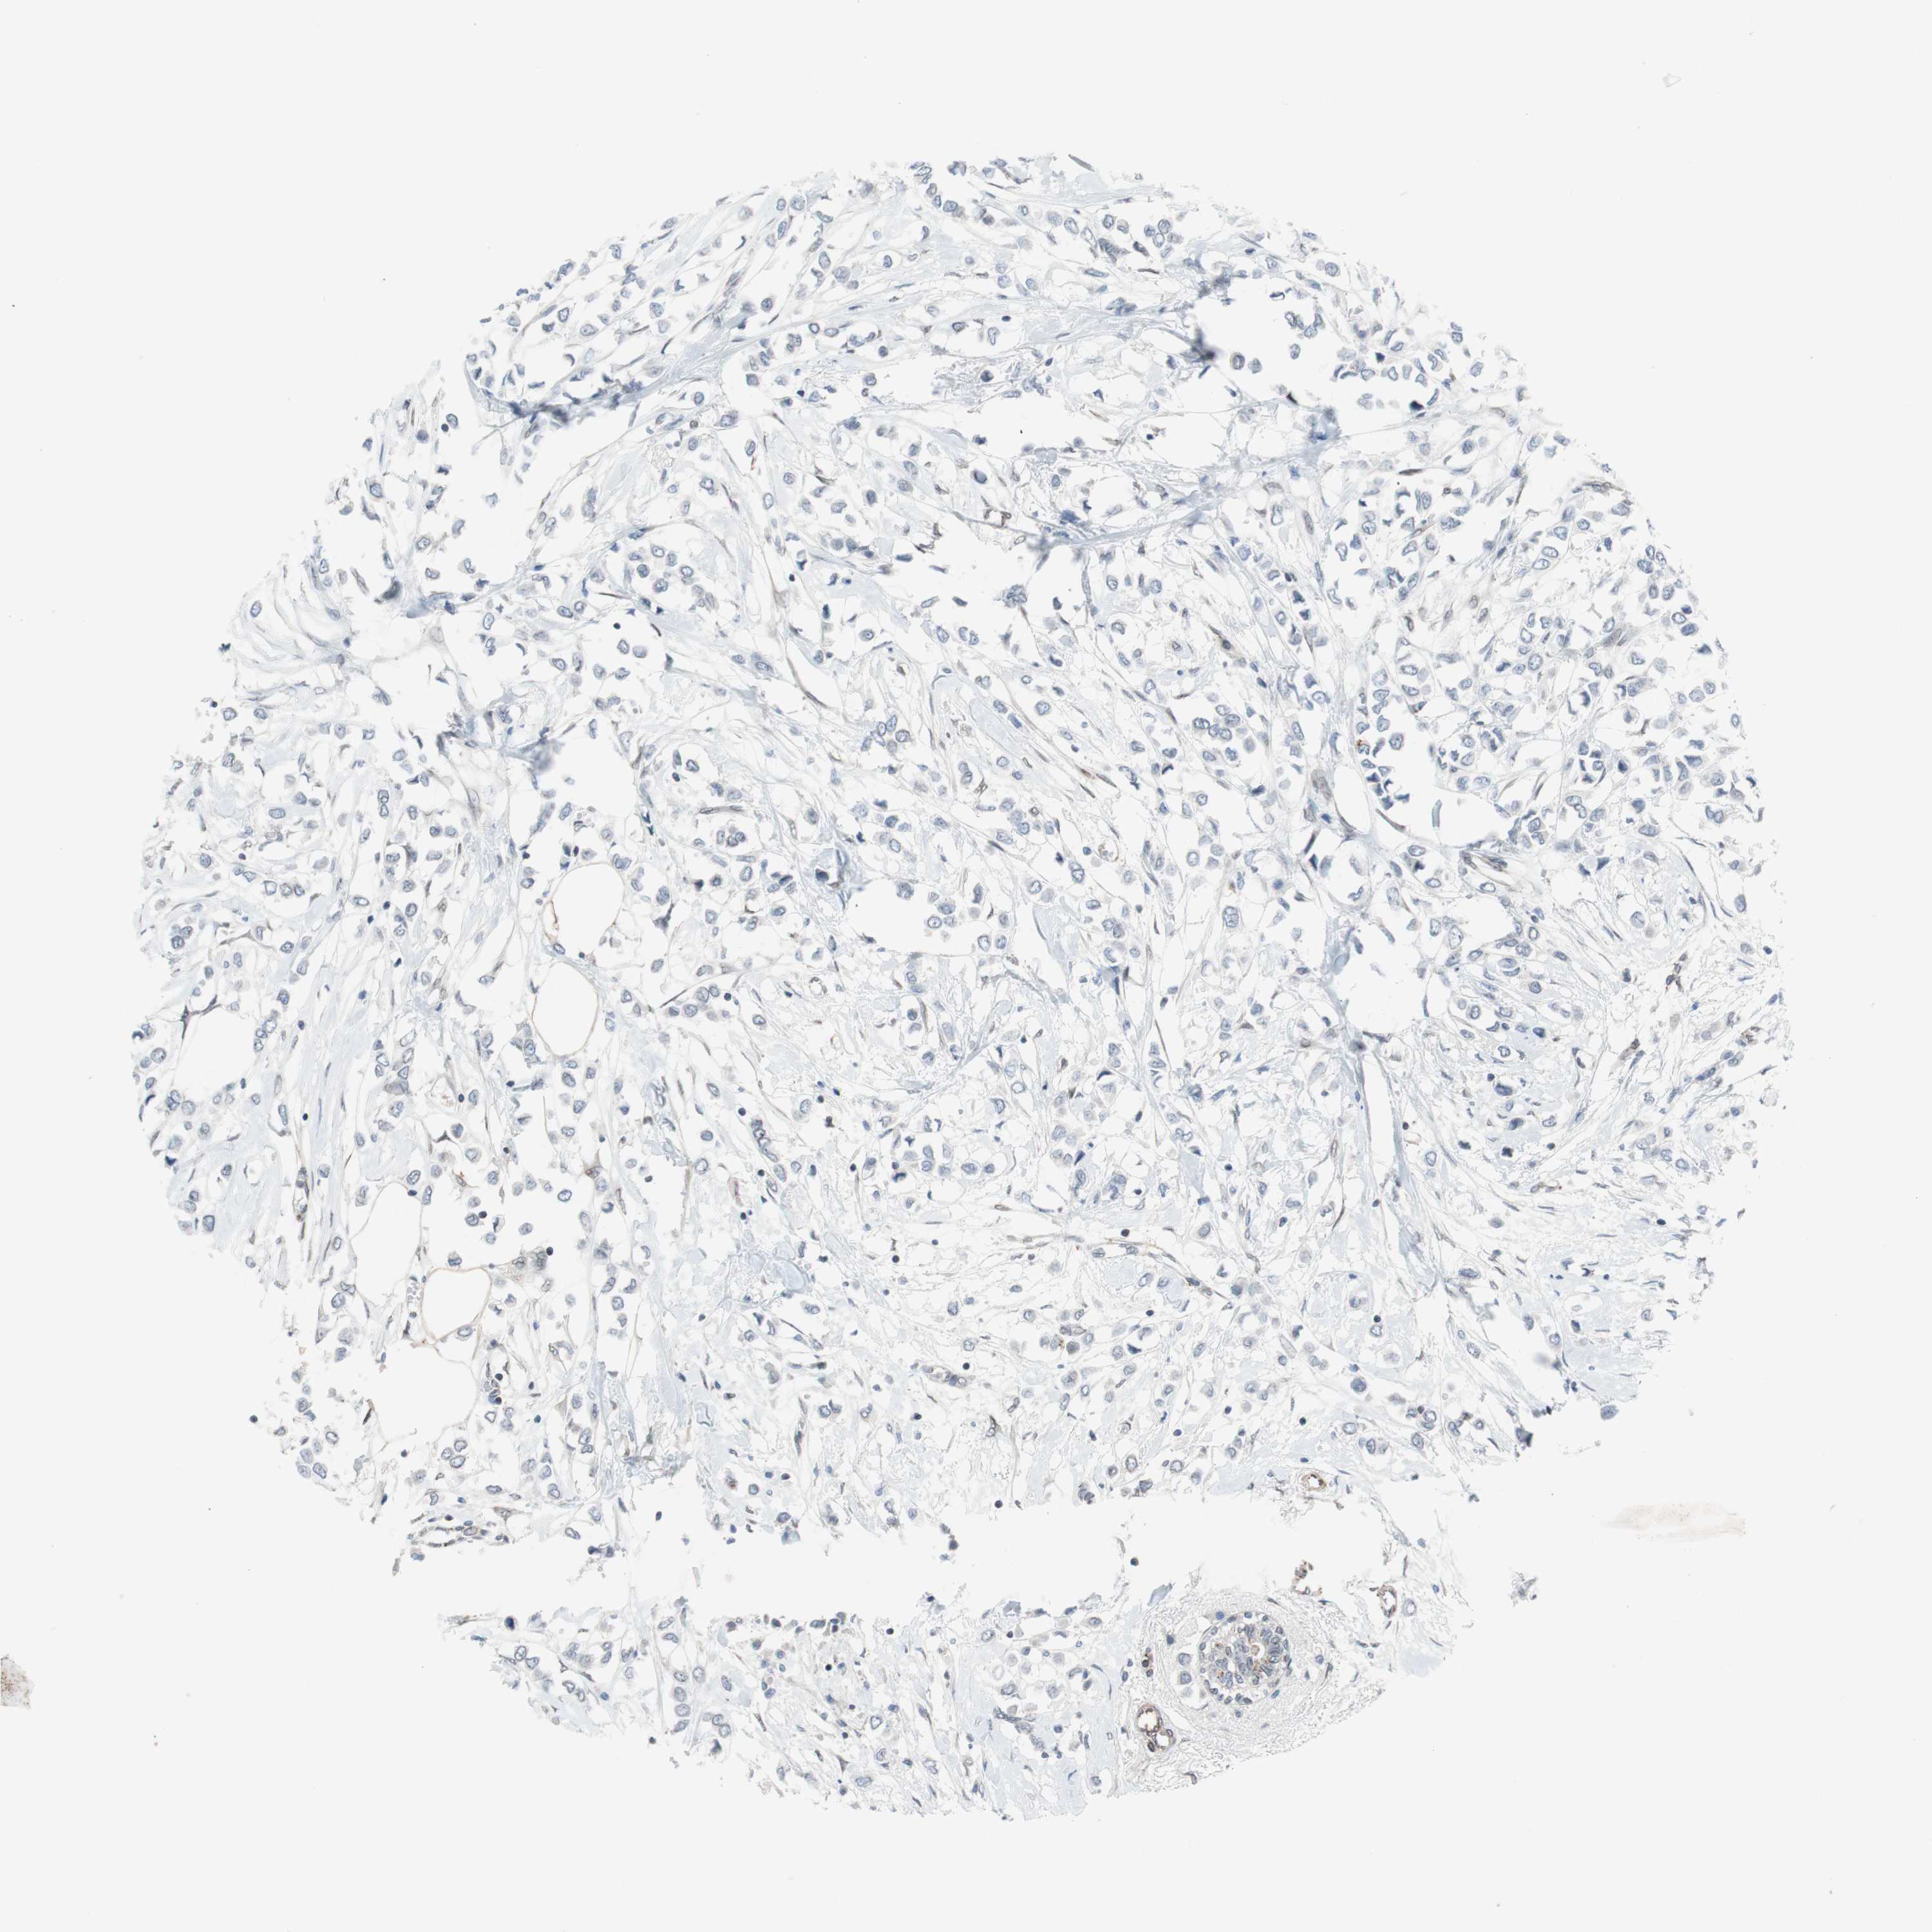

BRCA TCGA BRCA VALIDATION PROTEIN EXPRESSION